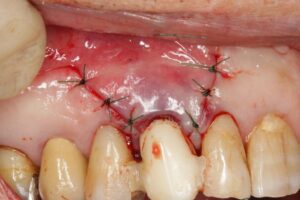

縫合